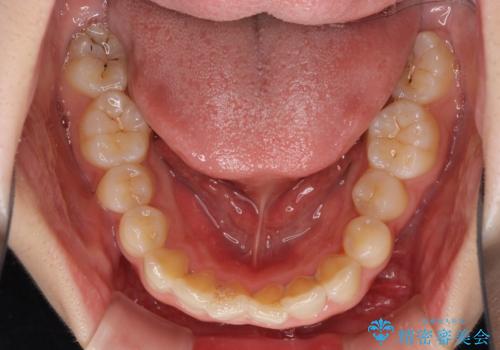

半年もせずにインビザラインを全く使用することができなくなってしまったので、治療開始から1年ほどでワイヤー矯正へ変更することとなりました。

ワイヤー矯正へ変更してからはあっという間に治療が進み、1年弱で終えることができました。